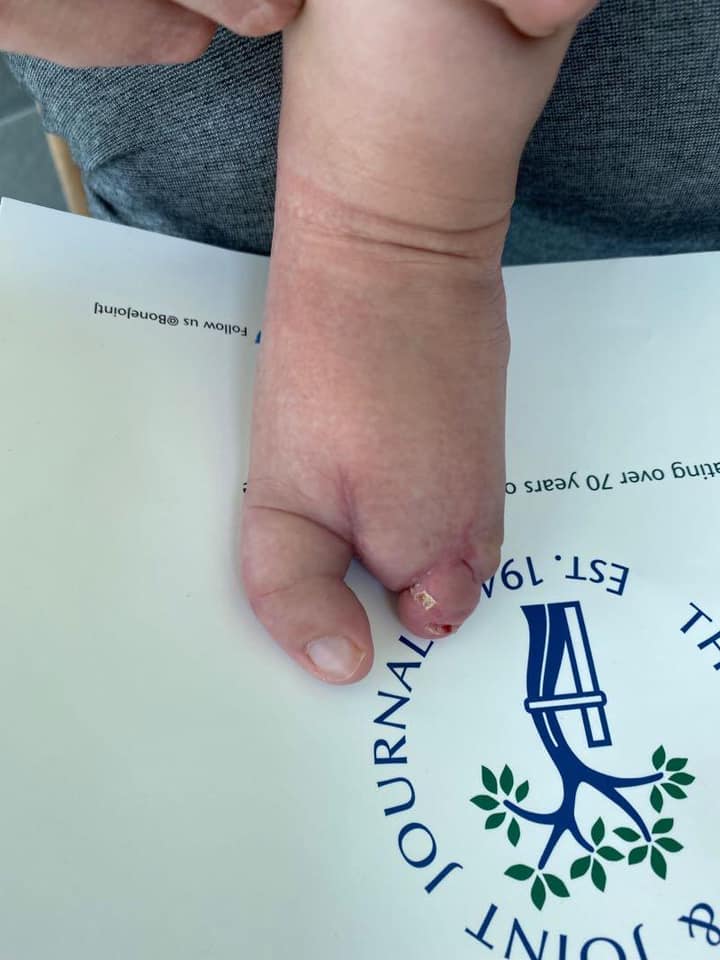

ectrodactilia deformidad en pie

Comparto el caso de mi pacientito Damián, quien me visitó por una deformidad en su pie llamada #ectrodactilia. Tuve la oportunidad de conocer su diagnóstico antes de que naciera, y a los 9 meses le realicé una cirugía de reconstrucción para la alineación del primer dedo, cierre del espacio y alineación del cuarto y quinto dedo. Aprovecho para felicitar a Damián, que hoy cumple 1 año y comienza a caminar sin dolor.